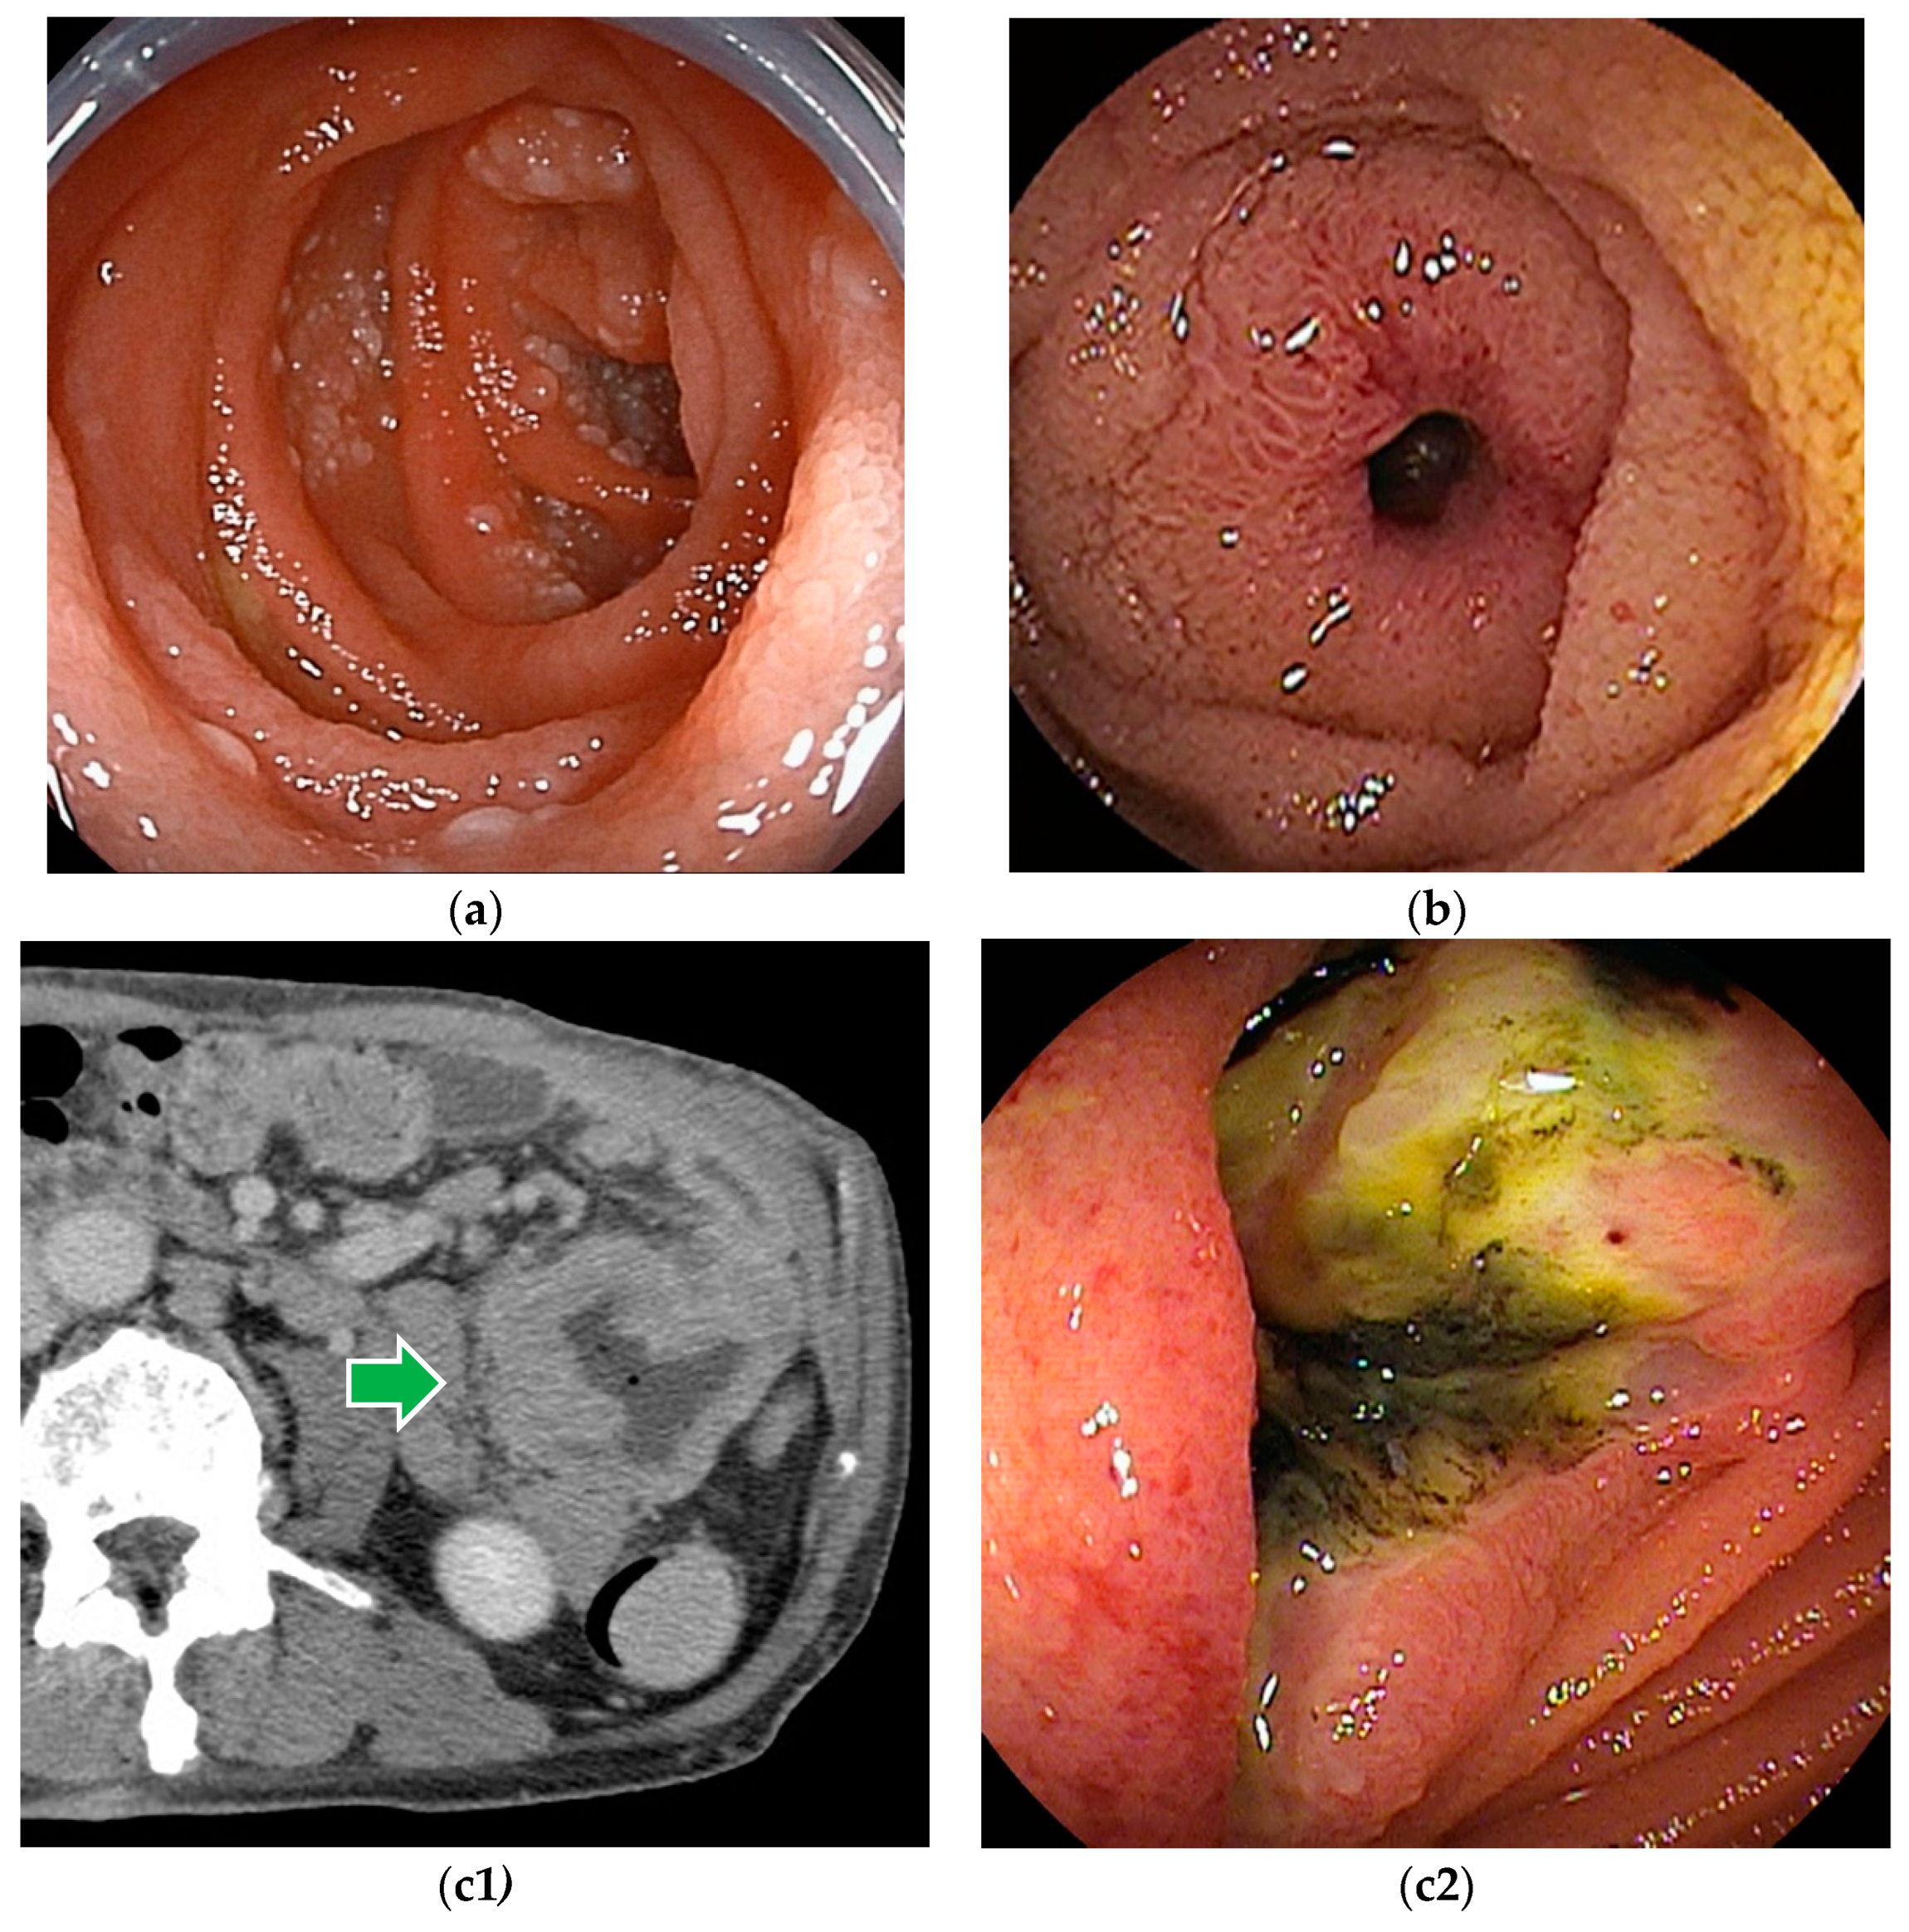

6.3. Malignant Lymphoma

6.4. Neuroendocrine Tumor

6.5. Metastatic Tumors

6.6. Benign Tumors